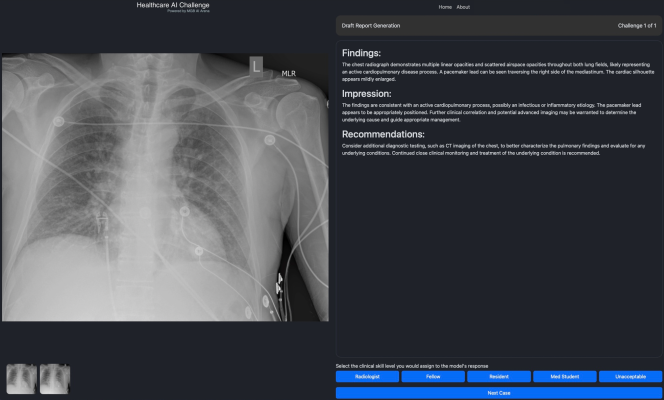

Participating healthcare professionals will be granted access to the Healthcare AI Challenge that features late breaking AI solutions they can assess for effectiveness on specific medical tasks, such as providing medical image interpretation, in a simulated environment. Participants with relevant healthcare credentials can then provide their feedback on the solutions’ performance and utility, which will generate publicly available insights and analytics. By crowdsourcing input from healthcare professionals, the Healthcare AI Challenge seeks to create continuous, consistent and reliable expert evaluations of AI solutions in medicine. Importantly, scaling the evaluation of these technologies and sharing the insights broadly and transparently can result in societal benefit for healthcare stakeholders and patients globally.

Health care professionals at instituyions that are a part of the Collaborative who register can log onto the Healthcare AI Challenge, select one of several events — such as image interpretation — and choose from a series of challenges to assess any one of the multiple foundation models available on the platform. The image interpretation challenges include questions focused on draft report generation, key findings, differential diagnosis, among others. The expert then rates the clinical skill level of the foundation models’ responses, which contributes to the insights and analytics rankings. Only verified healthcare professionals can participate in challenges that contribute to the rankings. The results of the Healthcare AI Challenge can be followed by the general public at HealthcareAIChallenge.org.